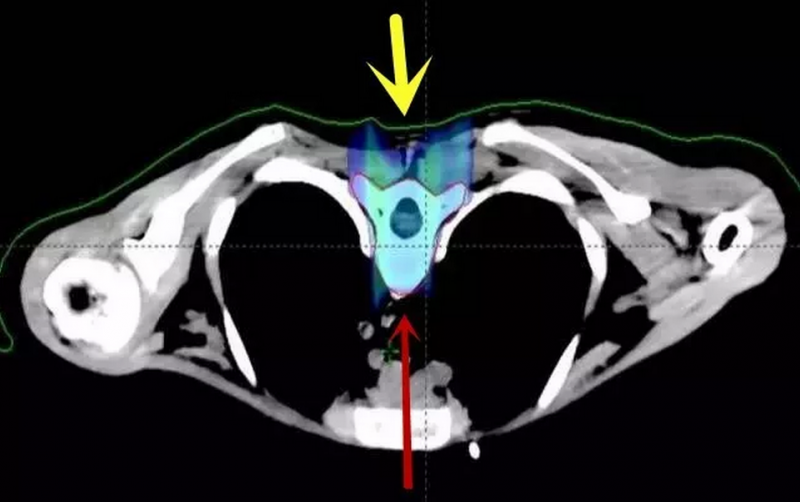

解析:这是髓母细胞瘤对脊柱照射剂量的分布图比较,上图是传统放疗的照射情况,我们可以看到箭头指示处是大面积的深棕色区域,这表示传统放疗会对身体造成大范围的损害,波及脊柱周边的脏器,而下图质子治疗则没有这样的损害。

以下为全脑全脊髓质子剂量分布图:脊柱周围心肺胃肠等器官均未受照射